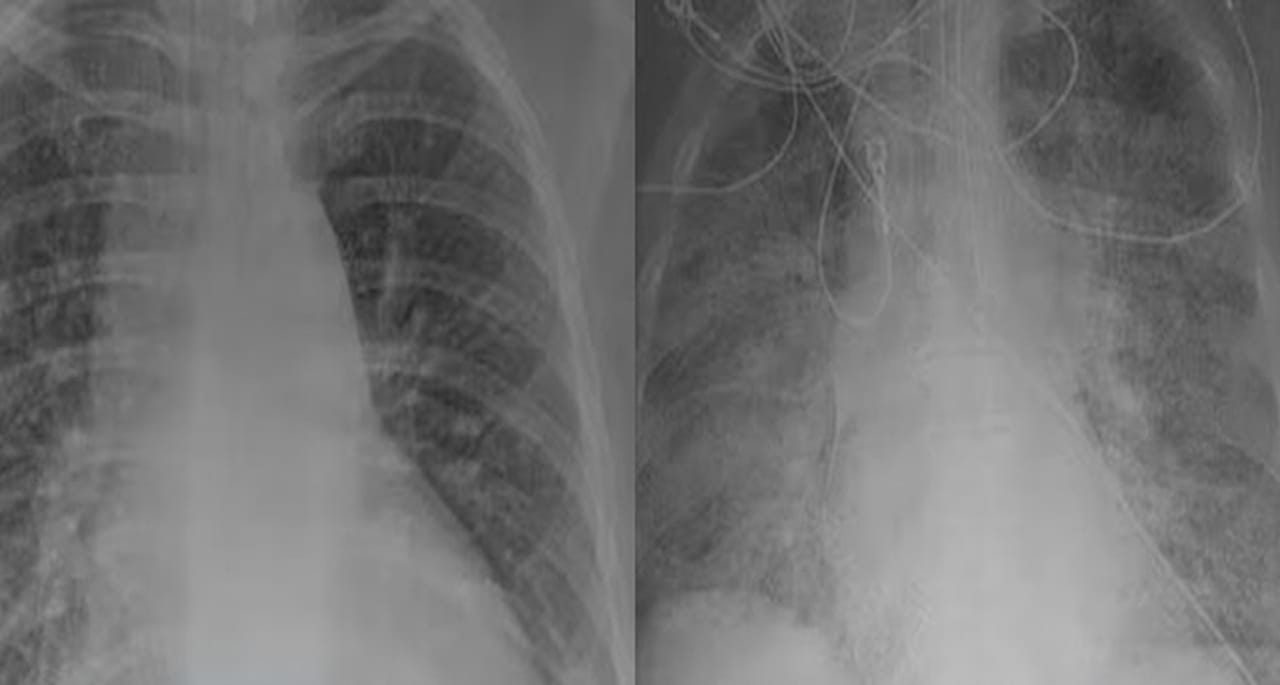

ڈاکٹر نے ویکسین شدہ افراد کے پھیپھڑوں میں آکسیجن کی آمدورفت دکھانے کے لیے دو ایکسرے کے نمونوں کا موازنہ پیش کر کے ویکسین کی اہمیت کو اجاگر کیا ہے۔

بغیر حفاظتی ٹیکے والے مریض کے پھیپھڑوں کا ایکسرے مکمل طور پر سفید آیا، جو ظاہر کرتا ہے کہ وہ وائرس سے اس قدر بھرا ہوا ہے کہ بری متاثر ہو چکا ہے۔ جبکہ یہ اعضاء میں داخل ہونے والی آکسیجن کی کمی کی بھی پیش گوئی کرتا ہے، جس سے سانس لینے میں دشواری پیدا ہونے کے بعد مریض کو وینٹی لیٹر کی ضرورت پڑ سکتی ہے۔

لیکن کورونا میں مبتلا ہونے کے بعد ویکسینیٹڈ افراد کے پھیپھڑوں کے سکین میں زیادہ تر جگہ سیاہ ہی تھی جس کا مطلب ہے کہ یہاں آکسیجن کی کوئی کمی نہیں اور زیادہ تر حصے پر وائرس کوئی اثر نہیں کر سکا ہے۔